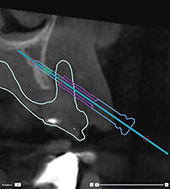

Correct inclination and depth of

anchor pins

To stabilize the surgical

template for implant insertion, anchor pins can be placed at strategic

positions. Their inclination

and depth are crucial.

The anchor pins can

also serve as lip retractors during surgery. Anchor pins spread too widely

within the arch could negatively affect mouth opening. A short-shaft version

of the anchor pin is available to mitigate this effect. Nevertheless,

the anchor pins should be planned so as to offer good access and should

not interfere with the implant sites.